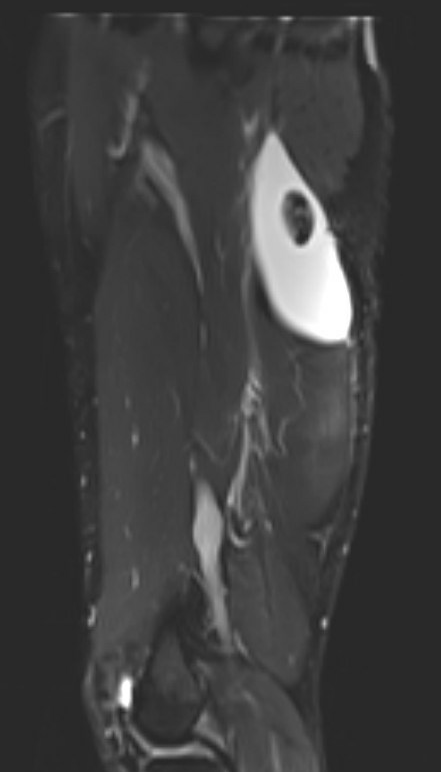

Proximal hamstring tear on right (red circle), normal insertion on tuberosity on left (blue circle)

Proximal hamstring tear on right (red circle), normal insertion on left (blue circle)